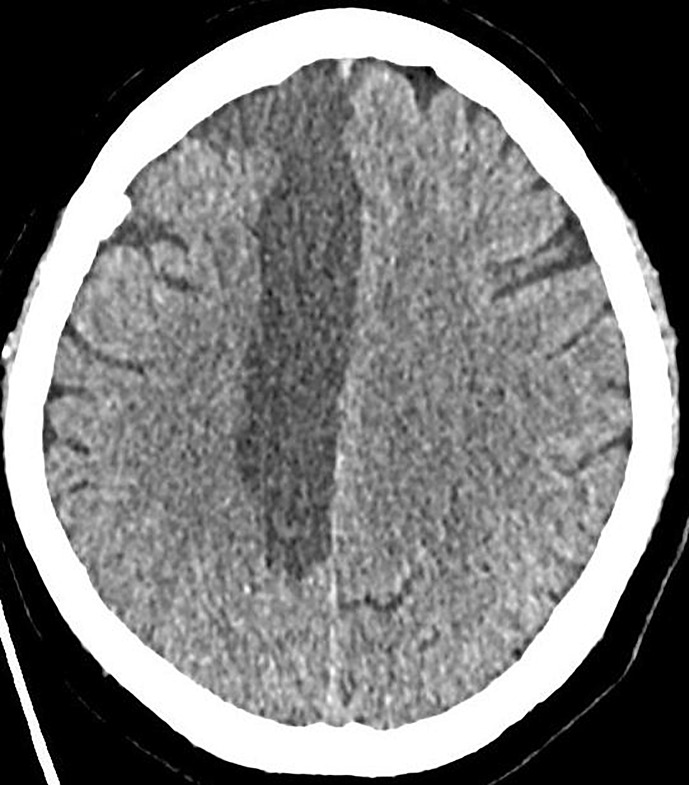

Case presentation: We present the case of a 54-year-old woman who developed akinetic mutism after infarction in the territory of the right anterior cerebral artery, successfully treated with methylphenidate and levodopa/benserazide. Clinical examination showed a patient lacking any spontaneous speech and movement while opening her eyes and fixating. Suspecting akinetic mutism after a comprehensive diagnostic work-up, we started an individual therapy attempt with methylphenidate 10 mg and levodopa/benserazide 100/25 mg twice daily. Both drugs affect the dopaminergic and noradrenergic transmission in the frontal-subcortical circuit, compromised in akinetic mutism. We saw rapid and sustained improvement in her volitional actions, devoid of side effects. Finally, the patient was actively communicating and moving her limbs.